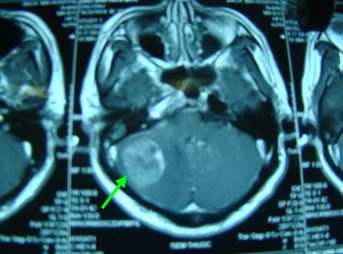

Chụp cộng hưởng từ sọ não

Kết quả: xuất hiện 1 khối tổn thương dạng thứ phát vùng bán cầu tiểu não phải kích thước 32x33mm, phù não quanh khối.

Chụp MRI sọ não

Trước điều trị: Xuất hiện 1 khối tổn thương dạng thứ phát vùng bán cầu tiểu não phải, kích thước 32x33mm, phù não quanh khối

Sau điều trị: Khối tổn thương dạng kén dịch vùng bán cầu tiểu não phải, kích thước thu nhỏ còn 14x12mm, không có phù não xung quanh

1. Tại não

· Khối u đã thu nhỏ kích thước (từ 33mm xuống còn 14mm), tổ chức khối u thoái hoá dạng nang (trên PET/CT, max SUV=3,54)

· Không có tổn thương mới